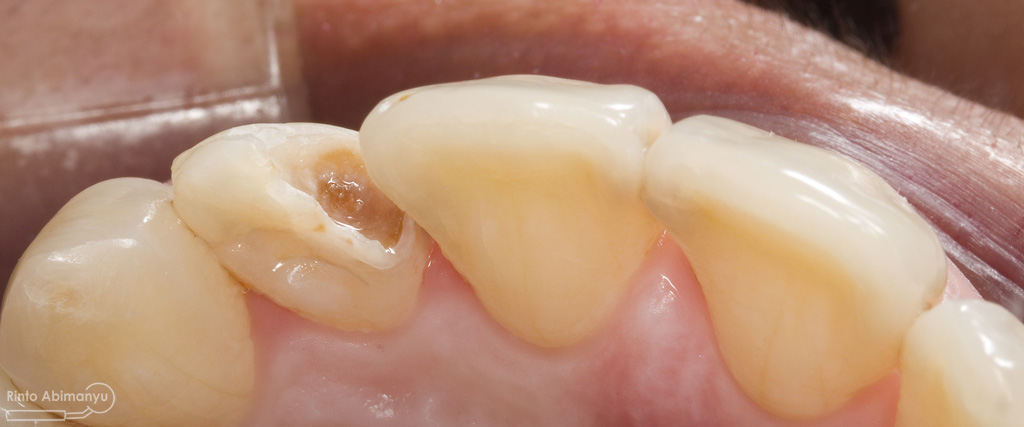

Pada pemeriksaan intra oral terlihat gigi 23 dan 24 mengalami karies dan cukup banyak sisa makanan terjebak disana…

Pemeriksaan respon dingin pun menunjukkan hasil negatif, untuk menambah data dalam penegakan diagnosis maka dilakukan pengambilan ronsen pada gigi2 tersebut

Terlihat dari ronsen tersebut karies pada gigi 23 24 sudah mencapai pulpa… dari informasi pemeriksaan klinis dan ronsen maka didiagnosis gigi tersebut nekrosis.. Saya jelaskan kepada pasien mengenai kondisi gigi2 nya dan rencana perawatan yang akan saya lakukan…